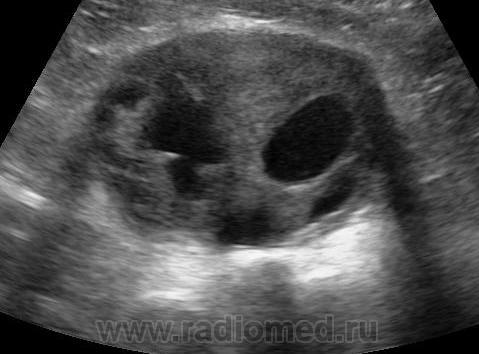

Пол пациента: Женский пол Тип патологии: Злокачественное новообразование Область исследования: Мочеполовая система Методы исследования: УЗИ Выглядит забавно. Но это не прикол и не фотошоп) Мой коллега обнаружил. У кого какие мысли что это и где? ID:33294 Thu, 14/11/2013 - 14:55 #1 Almo Offline Last seen: 2 days 14 hours ago Joined: 28.09.2008 - 18:50 Posts: 8281 Такая картинка может при многом и где быть... Навскидку :матка, простата. Thu, 14/11/2013 - 17:49 #2 Алексей Станисл... Offline Last seen: 5 years 11 months ago Joined: 11.08.2012 - 20:33 Posts: 1903 Что-то в клетчатке. Добро. В остальном - море вариантов. -1 к матке и простате. Яичник? С уважением, Thu, 14/11/2013 - 19:04 #3 И.Бондаренко Offline Last seen: 4 hours 3 min ago Joined: 13.09.2011 - 22:55 Posts: 9206 Моё мнение - яичник. А так - морда скунса. Thu, 14/11/2013 - 20:29 #4 vadim losevichev Offline Last seen: 7 years 2 months ago Joined: 27.01.2013 - 09:45 Posts: 679 Яичник. Non progrĕdi est regrĕdi. Thu, 14/11/2013 - 22:30 #5 Алексей Игореви... Offline Last seen: 6 years 11 months ago Joined: 08.08.2012 - 21:52 Posts: 786 Предположительное заключение - рак правого яичника. Сам ничего не скажу, в УЗИ не смыслю) Визуально у нас обозвали моргающей хеллоувинской тыквой "Обучая других - учишься сам". Н.И.Пирогов Fri, 15/11/2013 - 00:14 #6 Makcimalist Offline Last seen: 11 years 9 months ago Joined: 08.05.2010 - 14:28 Posts: 1994 Алексей Игоревич Чернявский wrote: Предположительное заключение - рак правого яичника. Не уточните размеры яичника (по УЗИ)?.. И размеры слайда (фото слайда)? -------------- "Просто, по видимости, не видеть логики в очевидных вещах - это тоже одно из свойств некоторых умов, наряду с грустными думами о свойствах ума других." © Vega 08/10/2011 Fri, 15/11/2013 - 13:52 #7 Алексей Игореви... Offline Last seen: 6 years 11 months ago Joined: 08.08.2012 - 21:52 Posts: 786 Говорил доктор, что вообще его не видно. Про размер слайда информации нет. "Обучая других - учишься сам". Н.И.Пирогов Sat, 16/11/2013 - 01:34 #8 Makcimalist Offline Last seen: 11 years 9 months ago Joined: 08.05.2010 - 14:28 Posts: 1994 Алексей Игоревич Чернявский wrote: Говорил доктор, что вообще его не видно. Про размер слайда информации нет. Интересно, каким датчиком его исследовали и во сколько раз увеличили (до таких размеров) то, что вообще не было видно... -------------- "Просто, по видимости, не видеть логики в очевидных вещах - это тоже одно из свойств некоторых умов, наряду с грустными думами о свойствах ума других." © Vega 08/10/2011 Sat, 16/11/2013 - 11:56 #9 Алексей Игореви... Offline Last seen: 6 years 11 months ago Joined: 08.08.2012 - 21:52 Posts: 786 Ну не знаю, коллега скинул мне картинку, в двух словах сказал, что он думает. А я просто ее выложил из за интересного вида. Ничего дополнить больше не могу. "Обучая других - учишься сам". Н.И.Пирогов

Такая картинка может при многом и где быть... Навскидку :матка, простата.

Что-то в клетчатке. Добро. В остальном - море вариантов. -1 к матке и простате. Яичник?

Моё мнение - яичник. А так - морда скунса.

Яичник.

Предположительное заключение - рак правого яичника. Сам ничего не скажу, в УЗИ не смыслю) Визуально у нас обозвали моргающей хеллоувинской тыквой

Не уточните размеры яичника (по УЗИ)?.. И размеры слайда (фото слайда)?

Говорил доктор, что вообще его не видно. Про размер слайда информации нет.